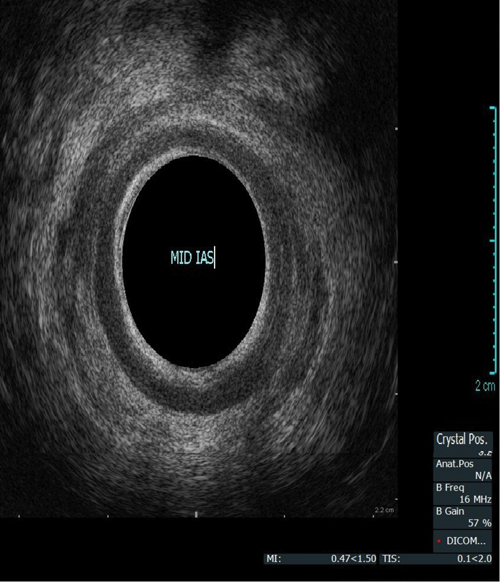

Endoanal ultrasound

This procedure is indicated for assessment of the anal sphincter in patients with incontinence. This allows evaluation of the internal and external anal sphincters (sphincter thickness, length and scarring). It is pertinent to obtain history of obstetric trauma as well as any surgeries / intervention to aid assessment.

As with the proctogram technique, the procedure is explained in detail and consent obtained prior, and the presence of a chaperone makes the patient more comfortable. Digital rectal examination is performed as a reference to assess anal tone. Still images as well as cine of the ultrasound are taken to assess the sphincter complex (Figure 3).

Figure 3a: (Top, middle and bottom) Normal endoanal ultrasound.

Figure 3b: Abnormal / deficient low internal anal sphincter.

Figure 3c: High External anal sphincter scars due to obstetric trauma.